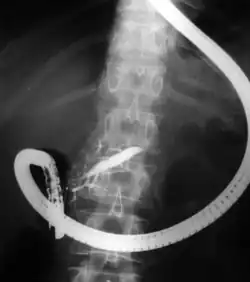

Fluoroscopic image of common bile duct stone seen at the time of ERCP. The stone is impacted in the distal common bile duct. A nasobiliary tube has been inserted.

The patient is sedated or anaesthetized. Then a flexible camera (endoscope) is inserted through the mouth, down the esophagus, into the stomach, through the pylorus into the duodenum where the ampulla of Vater (the union of the common bile duct and pancreatic duct) exists. The sphincter of Oddi is a muscular valve that controls the opening to the ampulla. The region can be directly visualized with the endoscopic camera while various procedures are performed. A plastic catheter or cannula is inserted through the ampulla, and radiocontrast is injected into the bile ducts and/or pancreatic duct. Fluoroscopy is used to look for blockages, or other lesions such as stones.[8][9]